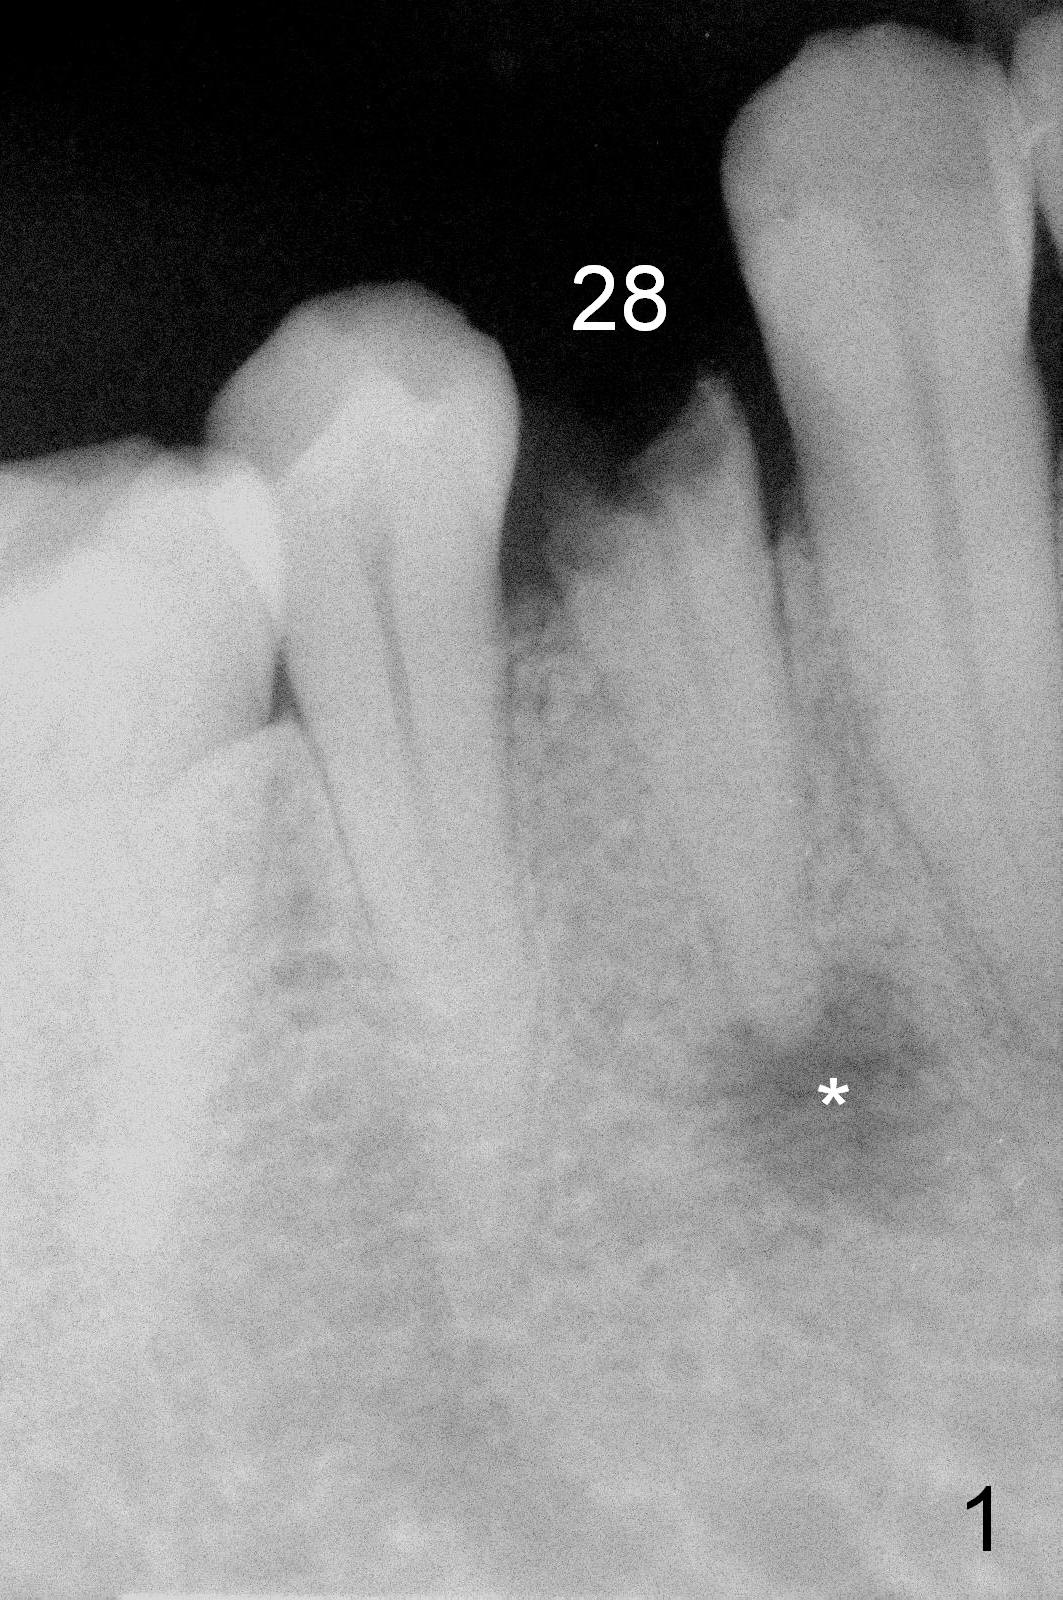

A 54-year-old man develops acute apical periodontitis associated with the tooth #28 (Fig.1). The latter appears to be non-salvageable with large periapical radiolucency (*). A 4.5x14 mm bone-level implant will be placed (Fig.2). The depth of osteotomy is to be tightly controlled after extraction (Fig.3 red long arrow) to avoid damage to the possible double Mental Loops (Fig.2 red dashed lines, 17 mm from the gingival margin). If the insertion torque is high, an immediate provisional is going to be fabricated. Bone graft is expected.